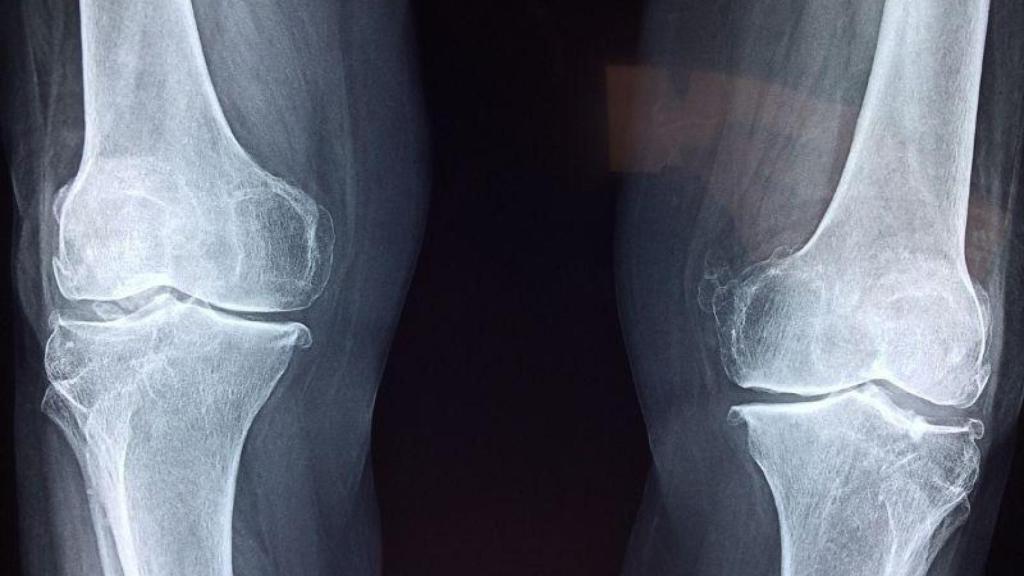

Artrosis